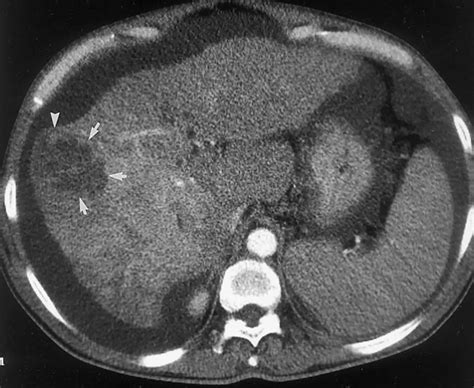

• Computed Tomography (CT) Scan: A CT scan provides detailed images of the liver and can help determine the size and location of the cyst.